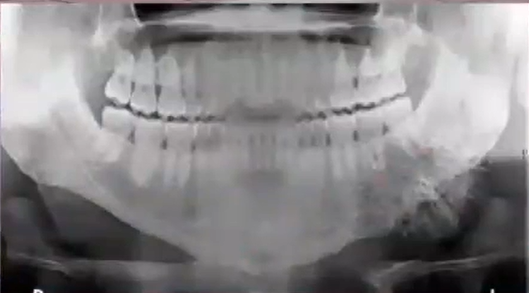

dx:

cementoblastoma

cemento-osseous dysplasia

condensing osteitis

fibrous dysplasia

cementoblastoma